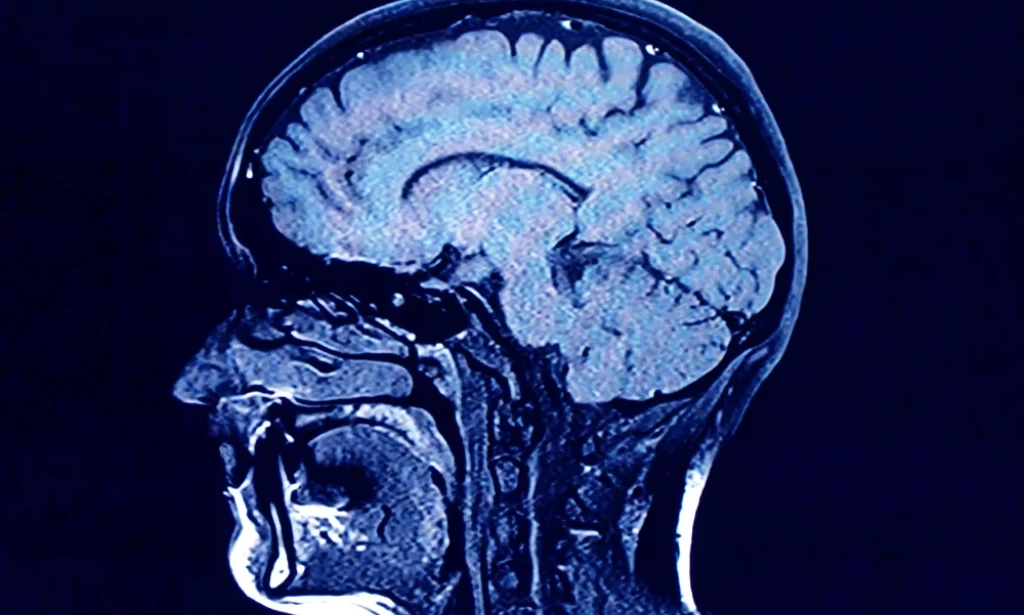

For their research, Mousley and her colleagues analyzed MRI diffusion scans — which are essentially images of how water molecules move within the brain — from about 3,800 people from newborns to age 90. The goal was to map the neural connections across the average person’s brain at different stages in life.

Based on the MRI scans, the new study maps the neural network of an average person across a lifespan, determining where connections are strengthening or weakening. The five “epochs” it describes are based on the neural connections the researchers observed.